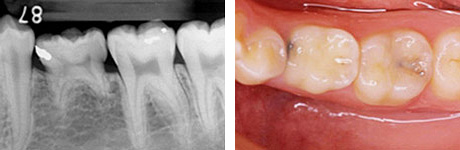

移植後4年。親知らずが第一大臼歯の代わりを担っています。

4年後。移植後に根が少し成長しているのが分かります。歯の神経もつながっています。